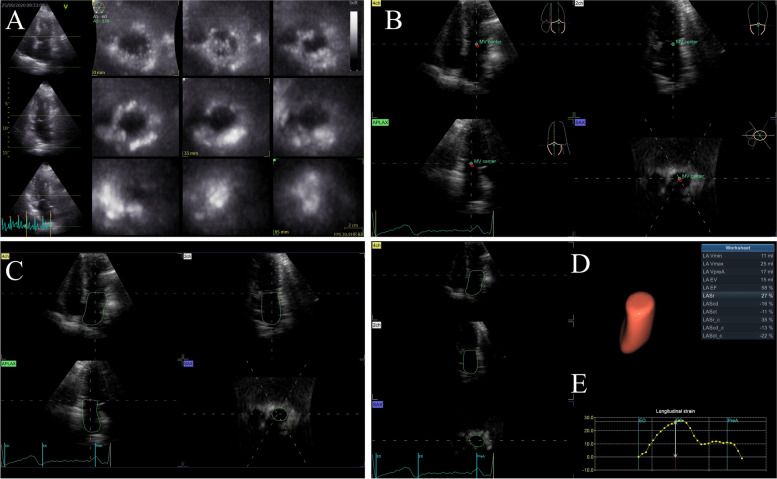

Background: Three dimensional speckle tracking echocardiography (3D STE) is a novel technique combining 3D echocardiography and speckle tracking analysis. 3D STE software dedicated to the left atrium (LA) was recently available. Our study aimed to assess (1) atrial fibrillation (AF) related LA morpho-functional remodeling using 3D STE and (2) value of LA function parameters in identifying paroxysmal AF (PAF).

Methods: One hundred thirty-nine PAF, 109 persistent AF (Per-AF) and 59 non-AF subjects underwent 3D STE. LA phasic volumes and total LA emptying fraction (LAEF) were obtained and used to calculate passive (pLAEF) and active LA emptying fraction (aLAEF) based on atrial contraction. LA longitudinal and circumferential strain representing reservoir (LASr/LASrc), conduit (LAScd/LAScdc) and pump (LASct/LASctc) function were also assessed.

Results: 3D STE was found to have good reproducibility. Increase of LA volumes and decrease of parameters representing LA reservoir and pump function were independently associated with AF as well as AF burden. The correlations between LA emptying fraction and LA circumferential strain representing the same function were always stronger than those with LA longitudinal strain (p < 0.001). Minimal LA volume, LAEF, aLAEF, LASrc and LASctc can be used to accurately differentiate PAF from non-AF subjects (AUC > 0.8) with great sensitivity and specificity.

Conclusions: Assessing LA remodeling in AF using 3D STE was feasible. AF and AF burden were independently associated with LA enlargement and impairment of reservoir and pump function but not conduit function. LA function parameters can indicate underlying PAF and thus can guide AF screening strategy.